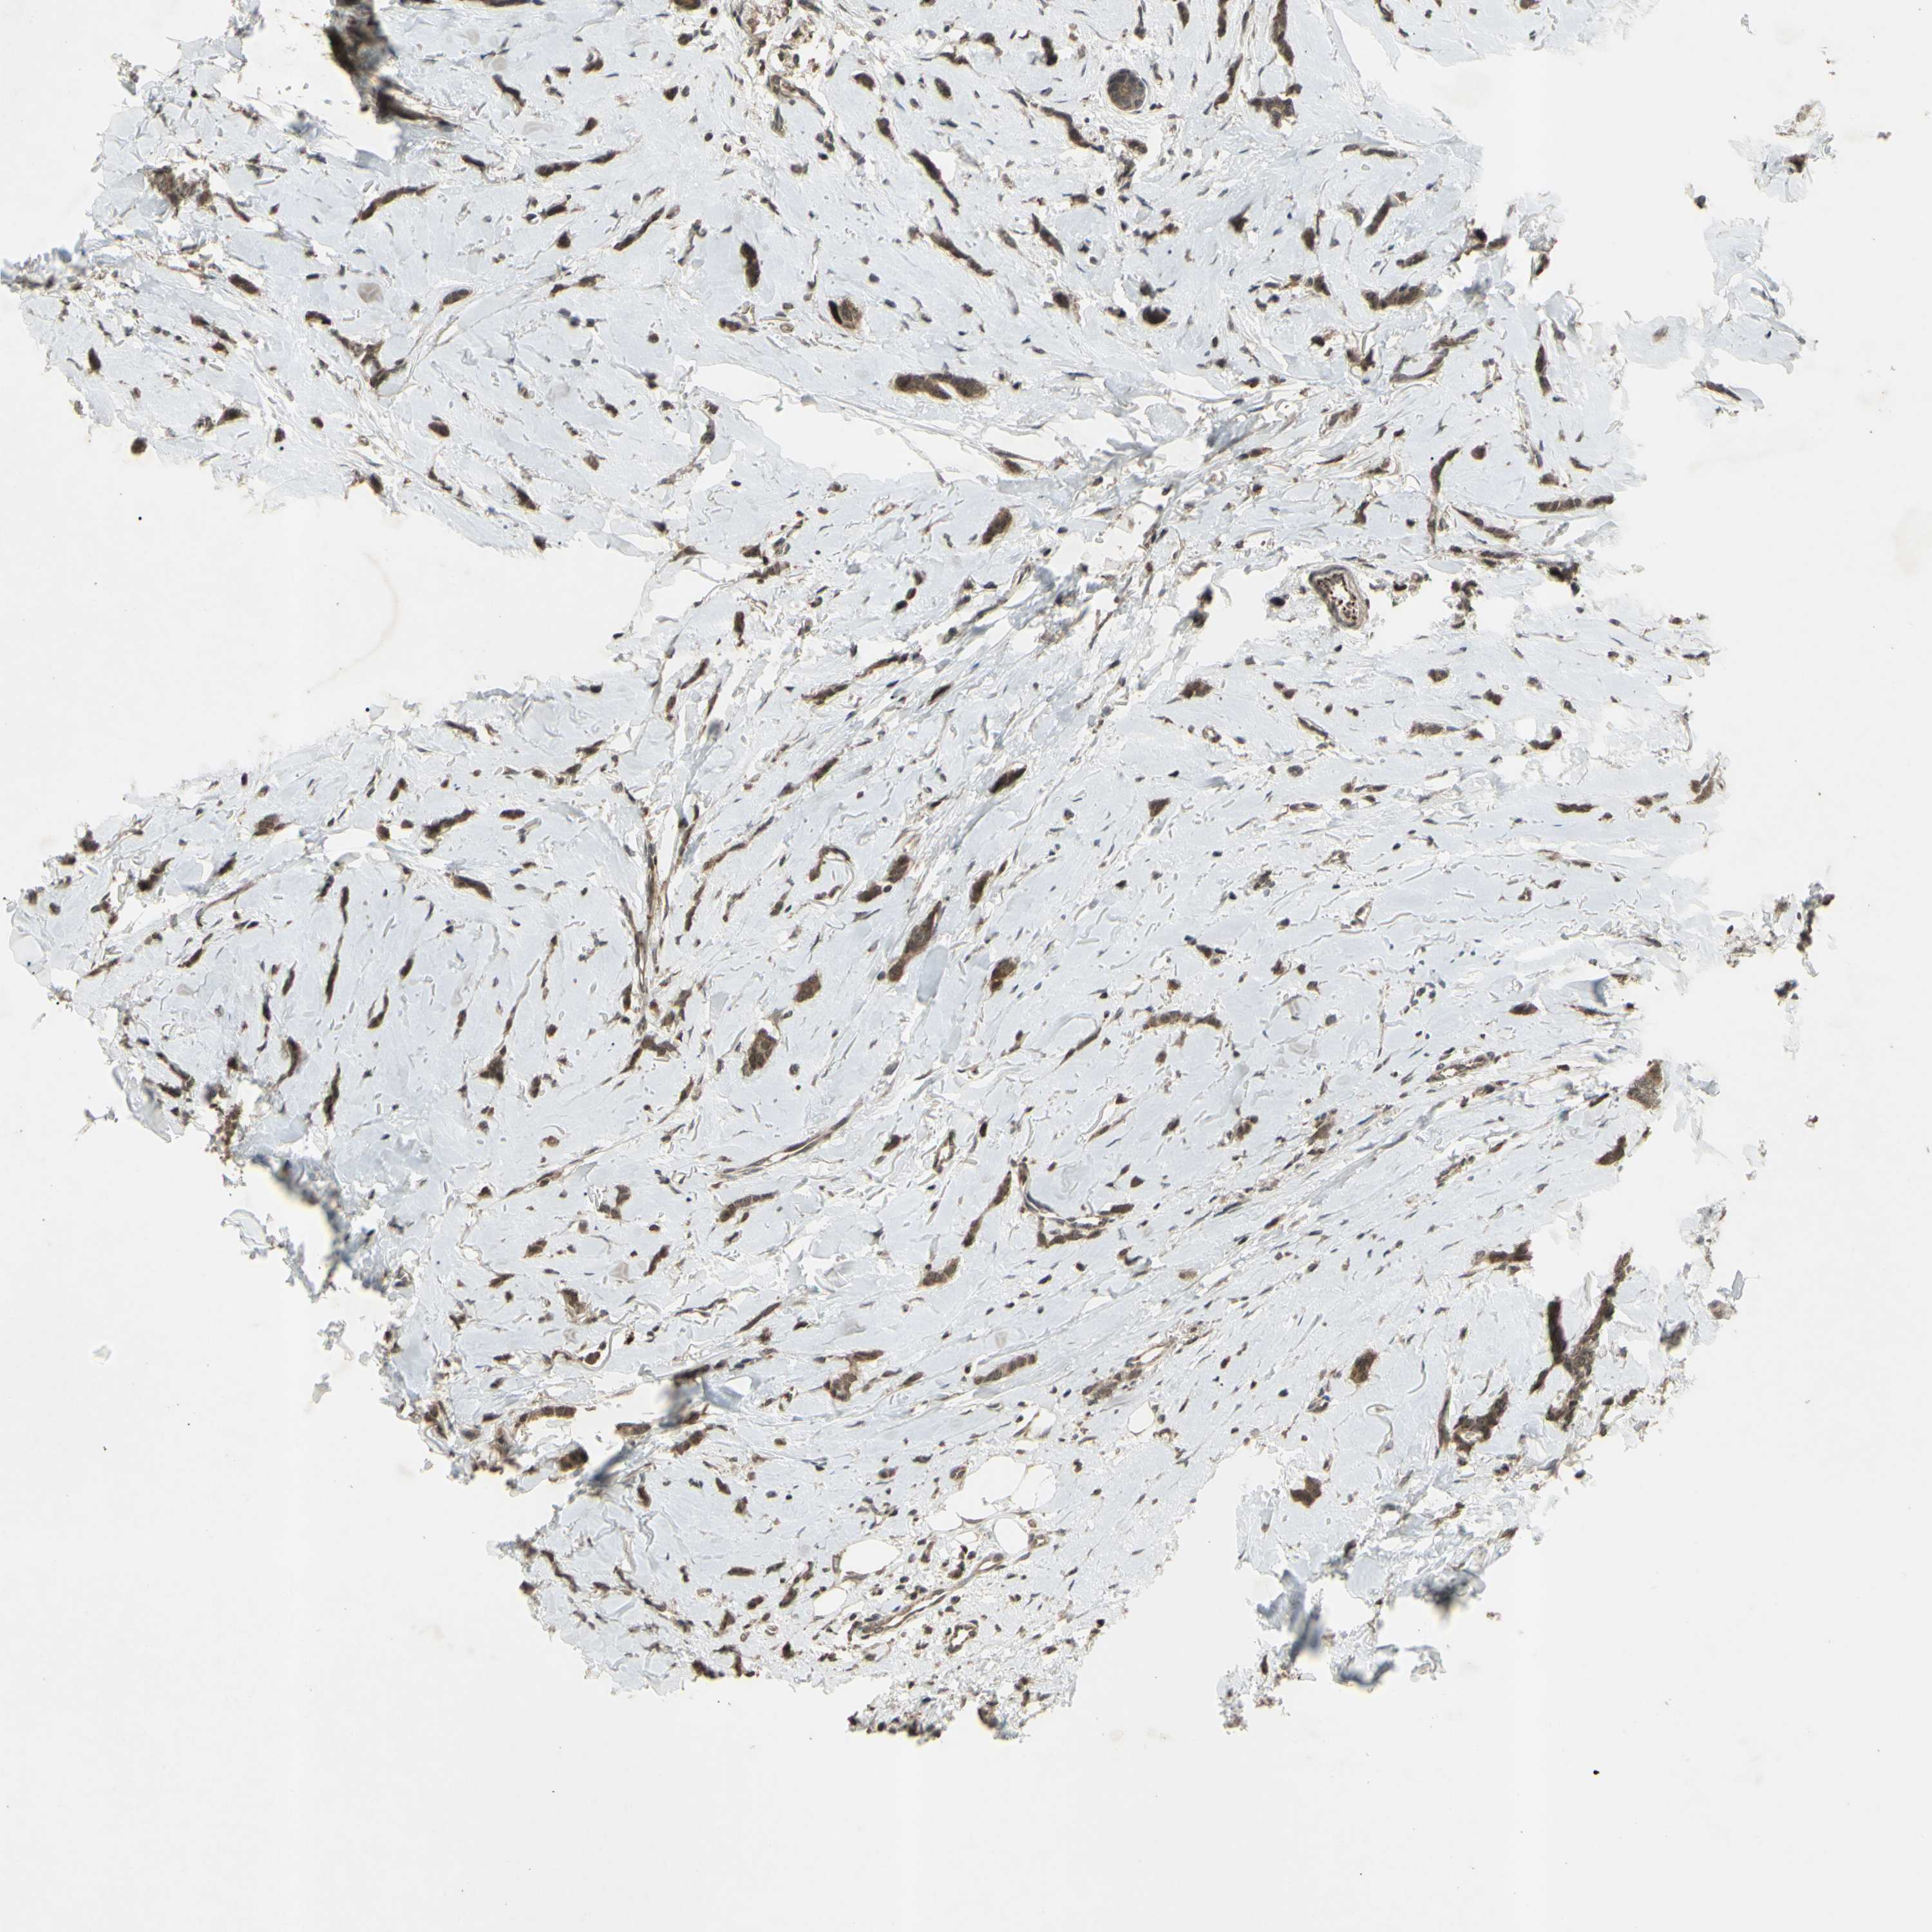

CANCER BREAST CANCER Show tissue menu

BRCA TCGA BRCA VALIDATION PROTEIN EXPRESSION